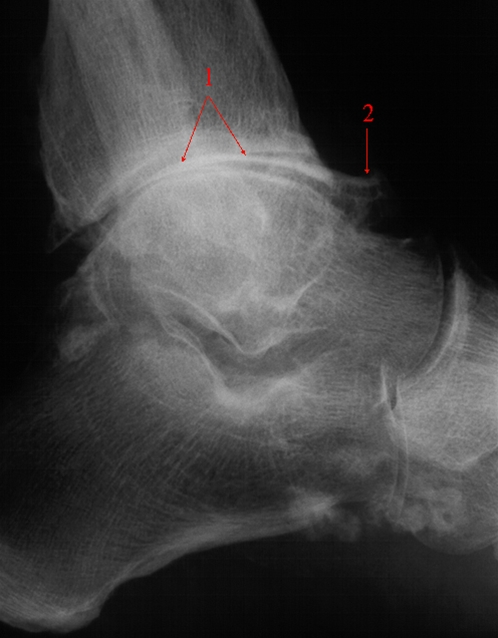

Diagnose kan evt. bekræftes ved røntgenundersøgelse. Den viser nedslidt brusk og eventuelt forandringer i selve knoglen, der ligger op mod brusken.

Ankelleddet består af knogler, der er dækket med et lag brusk. Ved slitage er det i første omgang brusken som bliver slidt ned. Med tiden kan brusken blive så nedslidt, at der er direkte kontakt mellem knoglerne.

Der kan også dannes såkaldte forkalkninger i leddet. Dette medfører, at der ikke længere er glatte ledflader, som glider mod hinanden, og det kan medføre mange smerter.